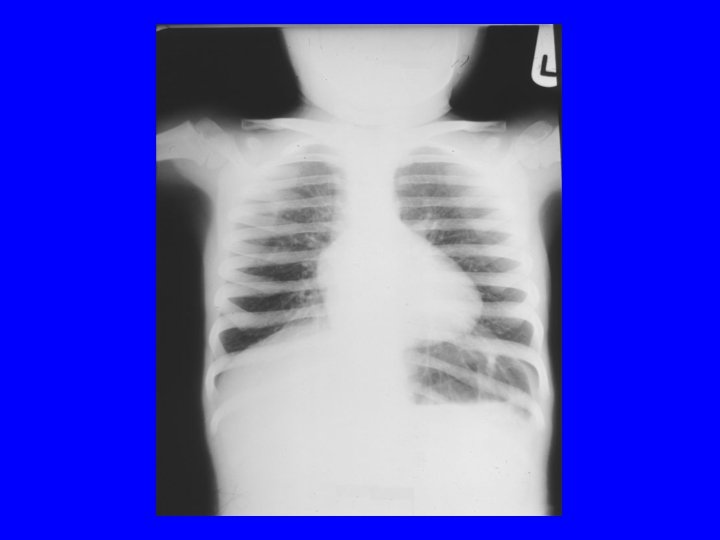

Case • An infant is delivered by c/s at 34 wk GA. There is no h/o ROM, maternal fever, or abn. FHR. The infant requires IPPV with a bag-mask and 100% O 2 in the delivery room. AS are 5 and 7. UA p. H was 7. 23. He is admitted to the WBN, but develops respiratory distress within an hour of life. RA ABG shows 7. 10/ 80/50/-10 with CXR

Transient Tachypnea of Newborn • It is a diagnosis of exclusion • Cause: delayed absorption of lung fluid • Risk factors: elective c/s, IDM, perinatal depression, precipitous delivery • Radiograph: Fluid in the minor fissure • Rx: supportive, resolves 2 -3 days

Meconium aspiration syndrome • Definition: MSAF+RD+CXR changes • Clinical: usually post-term, severe respiratory distress • Complications: pulmonary hypertension, airleak syndromes • CXR: snow storm appearance • Prevention: suctioning of meconium as per NRP protocol • Rx: respiratory support, correcting acidosis, antibiotics, surfactant